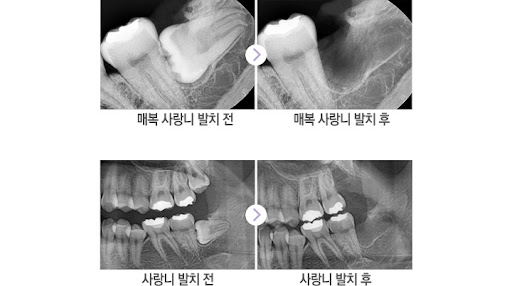

Comparison before and after wisdom tooth extraction